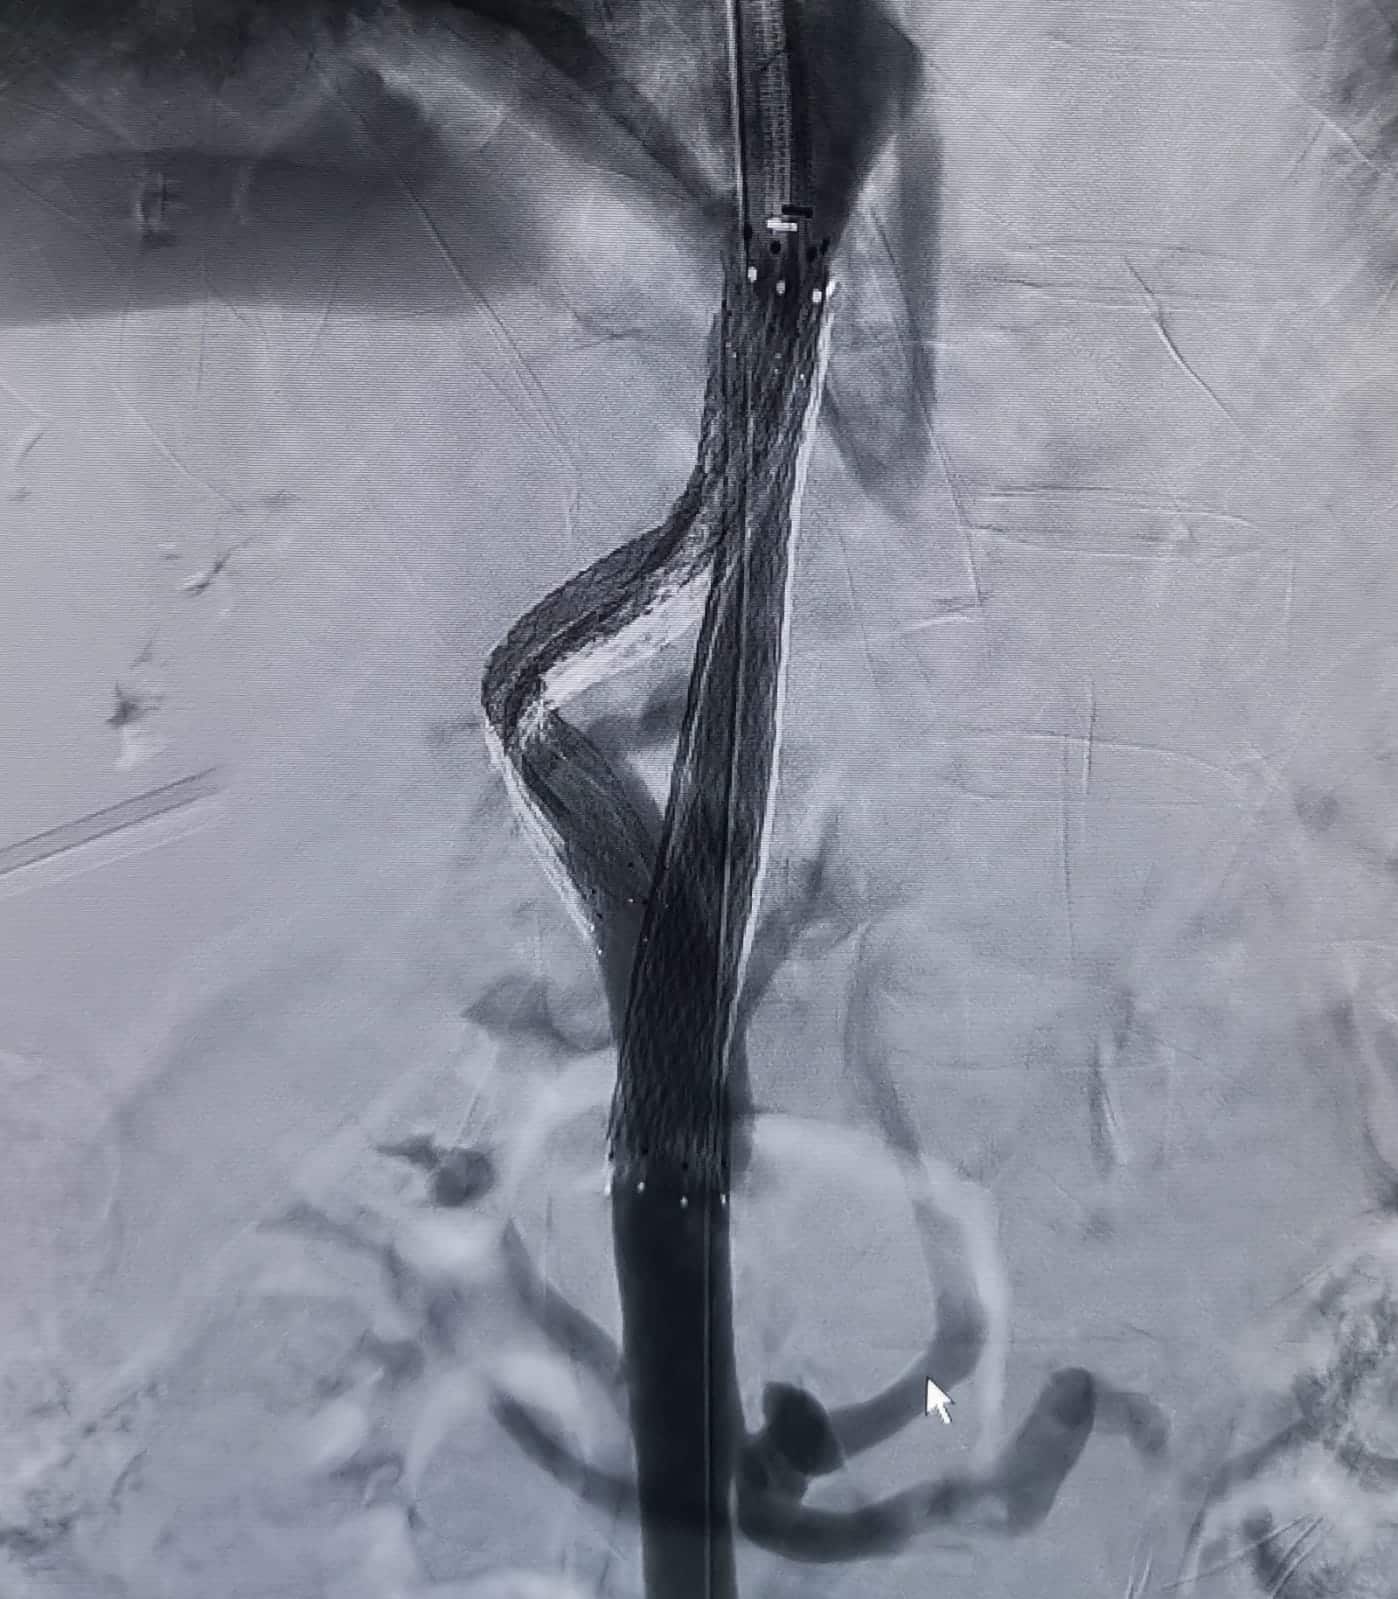

مستشفى الملك يجري عملية قسطرة معقدة داخل الكبد